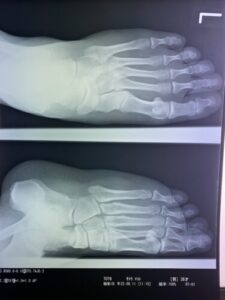

第5中足骨骨折の1症例について